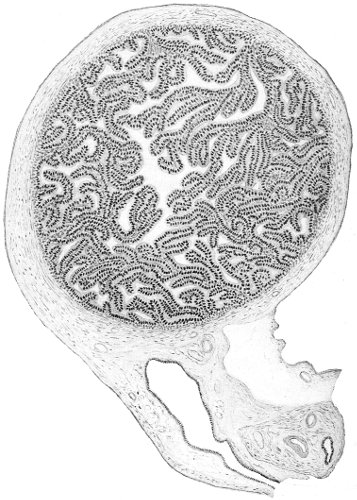

An accurate knowledge of the anatomy and mechanism of the female perineum is essential to an understanding of the nature and treatment of injuries to this structure. The anatomical structures lying between the anus behind and the symphysis pubis in front are those that most directly interest the gynecologist. Proceeding from 57 below upward, we find the following structures lying in superimposed planes: the skin, the superficial fascia, the deep layer of the superficial fascia, the transversus perinæi and the sphincter vaginæ muscles, the anterior layer of the triangular ligament, the posterior layer of the triangular ligament, the levator ani muscle (Fig. 19).

The vagina passes through these structures. They surround and support the ostium vaginæ as the fascia and muscles surround and support the opening of the rectum or the anus. The muscles and fasciæ are attached in the median line between the anus and the vagina, and therefore this part of the body, which is called the perineum, is supported or maintained in its 58 proper position by these various structures. The transversus perinæi arises from the ramus of the ischium and is inserted in the perineum. The bulbo-cavernosus, or sphincter vaginæ, arises in the perineum and is inserted in and about the clitoris. The inner fibers of the levator ani arise from the symphysis pubis and are inserted in the perineum and the lower part of the vagina (Fig. 20). When these muscles contract, their action, therefore, is to draw the perineum upward and forward. At the same time the anus is drawn upward and forward, and so also is the posterior margin of the ostium vaginæ and the lower portion of the posterior vaginal wall.

Fig. 20.—Dissection of female perineum, showing the deeper structures after removal of the levator and sphincter ani muscles.

The vagina has no circular sphincter like the anus, but 59 the vaginal month is kept closed by the action of the transversus perinæi, sphincter vaginæ, and levator ani muscles, which draw the perineum forward, and thus keep the posterior vaginal wall in apposition with the anterior wall.

Fig. 21.—Muscular floor of the pelvis seen from above.

This sling of muscles and fascia, which surrounds and supports the opening of the vagina, may readily be felt in the nulliparous woman by introducing the finger in the vagina and pressing backward and outward toward the ischio-rectal fossa. We then feel plainly, immediately within the ostium vaginæ, a firm resisting band of tissue, apparently about half an inch broad, embracing the posterior portion of the lower vagina. This band is formed by the inner edges of the various muscles and planes of fascia that have been described.